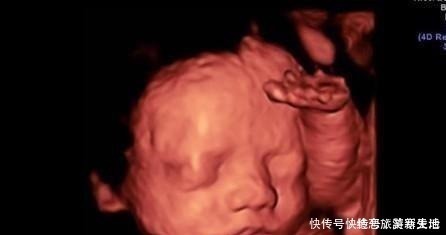

1.实时观察胎儿动态运动,检查胎儿生长发育情况。在怀孕期间,孕妈妈可以通过四维彩超得知胎儿在宫内的一些动态情况。比如说,通过四维彩超能够清楚的看到胎儿在宫内吞吐羊水,眨眼睛,吮吸手指,做鬼脸等动作。医生还可以通过四维彩超更清楚的看得到胎儿的发育情况,比如说血管畸形,体表畸形,内脏畸形等等,提前得知胎儿是否有唇裂,脊柱裂,骨骼发育不良,先天性心脏病等疾病,做到早知道早干预早治疗。2.图像清晰逼真。四维彩超相对于三维彩超更高清更精确,所以看起来更清晰,很多孕妈妈在做四维的时候就可以清晰地看到胎儿的五官,可以初步的判断一下胎儿到底长得像准爸爸还是准妈妈,所以,四维彩超也成为胎儿人生中的第一张照片。而不像二维一样,在大部分人看来就是黑坨坨的一片。【 好处|孕期做四维有什么好处,什么时候做最好这个时候做是最好的】